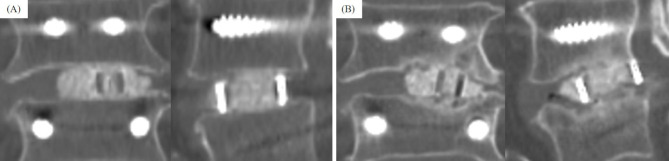

Methods: A total of 138 patients (mean age, 67 years; follow-up period, 12 months) who underwent single-level PLIF or TLIF were retrospectively analyzed. CS was defined as >1 mm sinking of the intervertebral cage evaluated via computed tomography. The patients were divided into the CS and nonsubsidence (NS) groups. HRQOL was assessed using the Oswestry Disability Index (ODI) scores.

Results: Among the 138 patients, 30 (22%) developed CS following PLIF or TLIF. All cases with TLIF surgery (n=25) involved the use of one cage. A significant difference was observed in the use of two cages between the CS and NS groups (20.0% vs. 48.1%; P=0.006). The CS group had lower occupancy rate of autograft soon after the operation than the NS groups (P=0.002), and the occupancy rate of autograft tended to decrease in the CS group compared with the NS group over time. The ODI scores improved in both groups postoperatively; however, the NS group exhibited greater improvements in ODI scores from 4 months postoperatively. The CS group had a significantly lower proportion of patients with intervertebral osseous union at 6 and 12 months postoperatively compared with the NS group (P=0.003 and P<0.001, respectively).